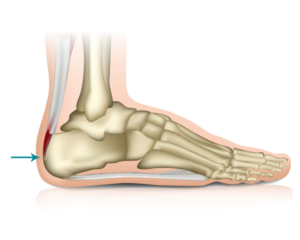

La Enfermedad de Sever o apófisis calcánea es una causa frecuente de dolor en el talón infantil. Suele aparecer entre los 7 y los 12 años de edad y es más frecuente en el género masculino y en aquellos niños que realizan actividad deportiva.

La apófisis calcánea es una inflamación aguda del cartílago por el desarrollo del talón. Durante el periodo de crecimiento se genera tensión muscular en el Tendón de Aquiles y la fascia del pie.